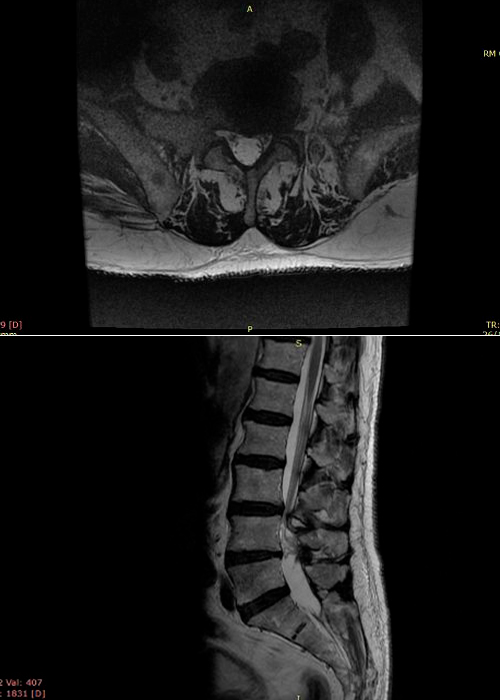

Preoperatorio

Paciente que acude a consulta por estenosis de canal, central con clínica de claudicación neurógena severa a partir de los 50 metros.

El paciente aquejaba de mucho dolor en ambos MMII por igual, reflejos disminuidos tanto aquíleo como rotuliano.

preoperatorio-estenosis-de-canal-instituto-cac

cirugia-estenosis-de-canal-instituto-CAC